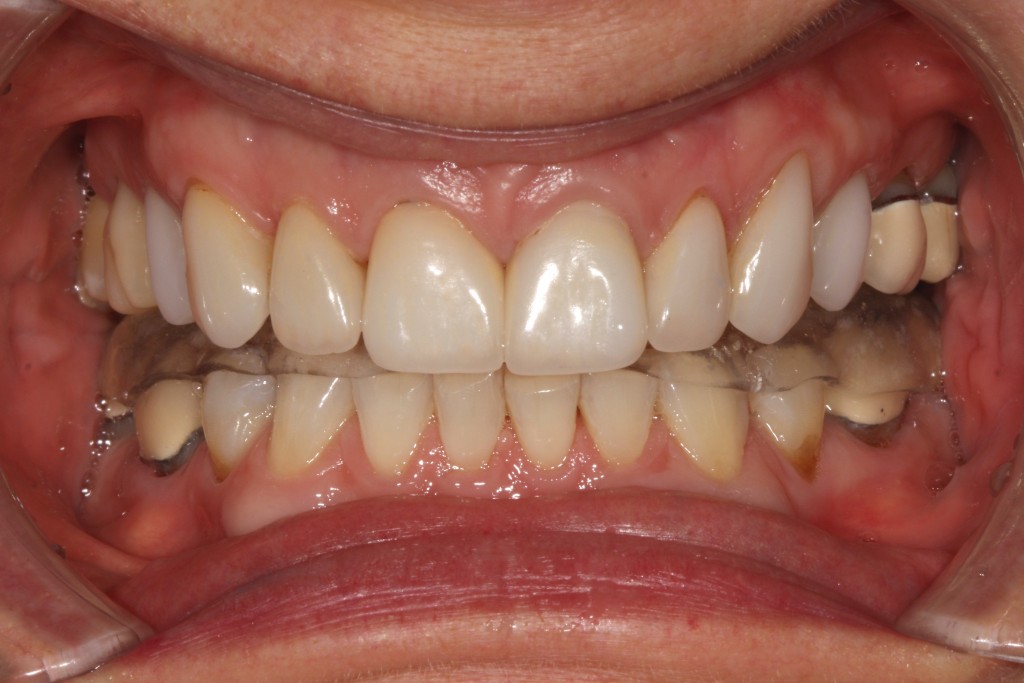

Over 40 million Americans suffer from Myofascial Pain Dysfunction (MPD), a condition that causes headaches and muscular pain. Dr. Klim uses advanced biofunctional diagnostic techniques to decrease painful tension in the head, neck, and shoulder muscles.

Many suffer from Myofascial Pain Dysfunction (MPD) and are not sure of the nature of their condition and how to solve it. You may have heard other terms that describe this condition such as TMJ or TMD. This is short for Temporomandibular Joints. Craniomandibular Dysfunction (CMD) or Temporomandibular Disorder (TMD) are another terms dentist use.